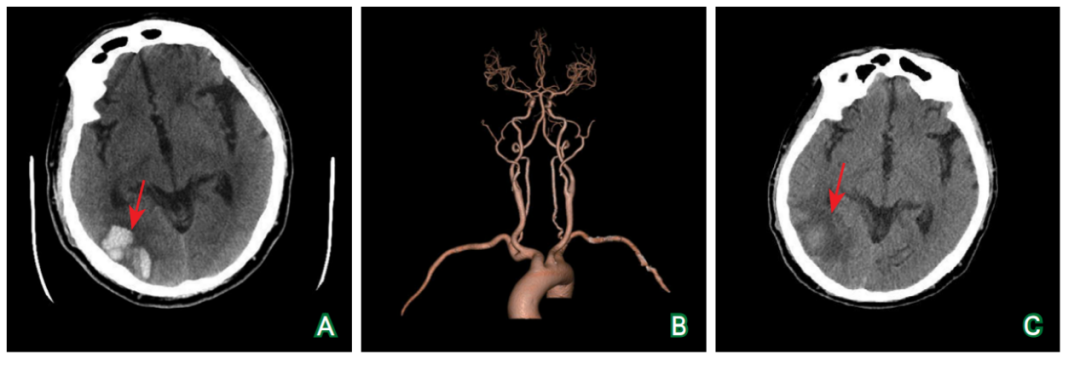

医脉通-临床病例平台 患者男性,67岁。主因“头晕1天,视物不清20小时”于2022年4月25日入院。患者入院前1天无明显诱因出现头晕,伴左侧视物不清、恶心,无 既往史: 入院查体:左上臂血压126/71 mmHg(1mmHg=0.133kPa)、右上臂血压132/70 mmHg,心率54次/分,律齐。神清语利;定向力、记忆力正常,计算力、判断力减退;颈软,Kernig征阴性;双侧瞳孔等大等圆,对光反射灵敏,眼球各方向活动正常,眼震未见异常,左侧视野同向偏盲;双侧额纹、鼻唇沟对称,伸舌居中;四肢肌张力正常,肌力Ⅴ级,共济稳准;感觉系统未见异常;四肢肌腱反射对称(++),双侧Babinski征(+),双侧掌颌反射(+)。NIHSS评分2分。 实验室检查(2022-04-26):空腹血糖7.3 mmol/L↑、 影像学检查:头颈部CTA(2022-04-26)示双侧颈总动脉、颈内动脉、颈外动脉、锁骨下动脉及无名动脉显示清晰,未见有意义狭窄或局限性扩张;双侧椎动脉均衡供血,走行自然,显示清晰,未见狭窄及局限性扩张;双侧大脑前动脉、大脑中动脉、大脑后动脉及基底动脉走行分布正常,未见明显狭窄;大脑前交通动脉可见显示,后交通动脉未见开放(图1B)。回顾既往影像检查,头颅MRI和SWI(2022-04-03)示双侧额叶皮质下、顶叶皮质下、颞叶皮质下、枕叶皮质下、半卵圆中心、侧脑室旁白质以及基底节区见多发点片状等/稍长T1信号、稍长T2信号,FLAIR为高信号;双侧额叶、顶叶、颞叶、基底节区、丘脑可见SWI低信号(图4)。MMSE评分25分,MoCA评分16分。 诊疗经过:入院后给予20 %甘露醇125 mL静脉输注,1次/8小时;0.9 %氯化钠溶液500 mL+15%氯化钾10 mL静脉输注,1次/日;继续服用二甲双胍,500毫克/次,3次/日;停用阿司匹林和阿托伐他汀。5月16日查体:左侧视野同向偏盲,双侧Babinski征(+),双侧掌颌反射(+)。NIHSS评分2分。复查头颅CT(2022-05-16)示右侧枕叶团片状稍高密度影,较4月25日头颅CT密度明显减低,周围环绕脑组织低密度改变(图1C)。遂出院,门诊随诊。 A:头颅CT(2022-04-25)示右侧枕叶多发团片状高密度影,周围环绕脑组织水肿(箭头所示);B:头颈部CTA(2022-04-26)示颅内外动脉未见明显狭窄及局限性扩张;C:头颅CT(2022-05-16)示右侧枕叶团片状稍高密度影,周围环绕脑组织低密度改变,较4月25日明显好转(箭头所示)。 图1 头颅CT平扫及头颈部CTA扫描结果 黑色箭头所示为先证者(患者);患者父亲、1个同父异母的哥哥有偏头痛病史并均已去世。 图2 患者的偏头痛家系 基因检测提示c.1774C>T杂合突变(红色圆圈所示) 图3 NOTCH3基因检测 A:T1WI序列双侧皮质下、侧脑室旁白质及基底节区可见多发点片状稍长T1信号(箭头所示);B:T2WI序列上述部位可见多发点片状稍长T2信号(箭头所示);C:FLAIR序列脑室旁、皮质下白质可见点片状高信号(箭头所示);D:SWI序列双侧额叶、顶叶、颞叶、基底节区、丘脑可见低信号(箭头所示)。 图4 头颅MRI平扫结果(2022-04-03) 患者最终诊断是什么?其常见临床表现有哪些?其并发脑出血的危险因素都有哪些? (查看原文参与互动讨论)